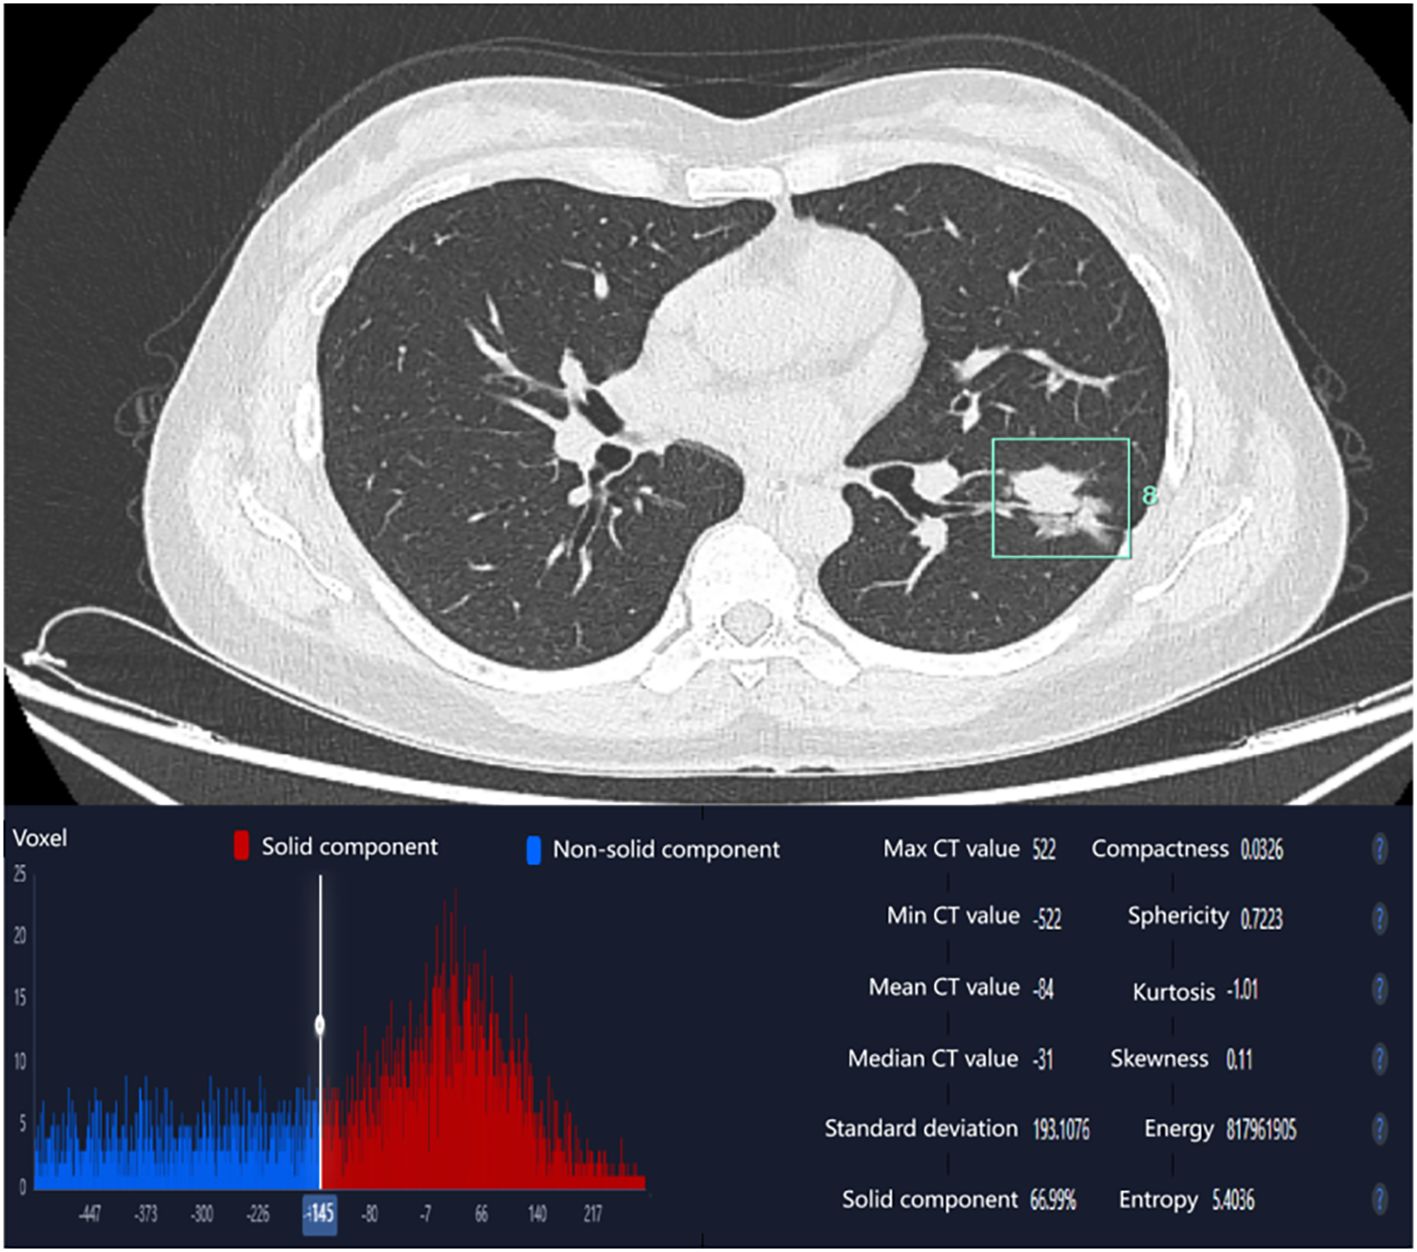

Lesion delineation was independently performed by two radiologists (one attending radiologist and one resident radiologist), both blinded to patients’ clinical information and EGFR mutation status. The consistency of the observers’ measurement results was analyzed using the ICC. Final results were derived from the average measurements of both radiologists. In cases of significant interobserver discrepancy, a third senior radiologist with subspecialty expertise in thoracic imaging arbitrated the final determination. Representative images are shown in Figure 1.

Figure 1. Spectral enhancement image with ROI delineation and spectral curves. ROIs were placed at the largest cross-sectional dimension of the tumor, encompassing the majority of solid components within the lesion. (a, b) EGFR wild-type (female, 45 years old; λHU = 1.59); (c, d) EGFR mutation-positive (female, 50 years old; λHU = 2.21).